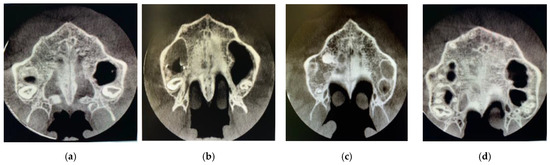

Subsequently, visualization and classification of the skeletal maturation stage of the midpalatal suture according to Angelieri’s method was performed on the CBCT axial slices themselves [14] Figure 3.

Figure 3.

Axial slices of the different stages of the suture in the study. Stage B (a), stage C (b), stage D (c) and stage E (d).